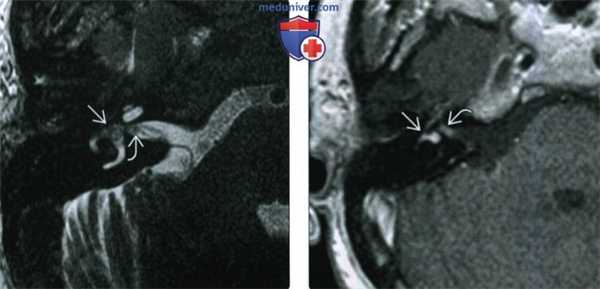

(Слева) При аксиальной МРТ Т1 ВИ визуализируется экспансивное дольчатое объемное образование левой височной кости с участками ↑ Т1 сигнала, которые часто обнаруживаются в ОЭЛМ и обычно расположены на периферии.

(Справа) При аксиальной МРТ Т1 С+ FS у этого же пациента определяется типичное интенсивное неоднородное контрастное усиление, ожидаемое при ОЭЛМ. Эта опухоль также прорастает в левый ВСК, среднее ухо в и сосцевидный отросток. Обратите внимание на диффузный патологический сигнал в левом глазном яблоке, свидетельствующий об ангиоме сетчатки с отслойкой, наблюдающейся при болезни фон Гиппеля-Линдау.